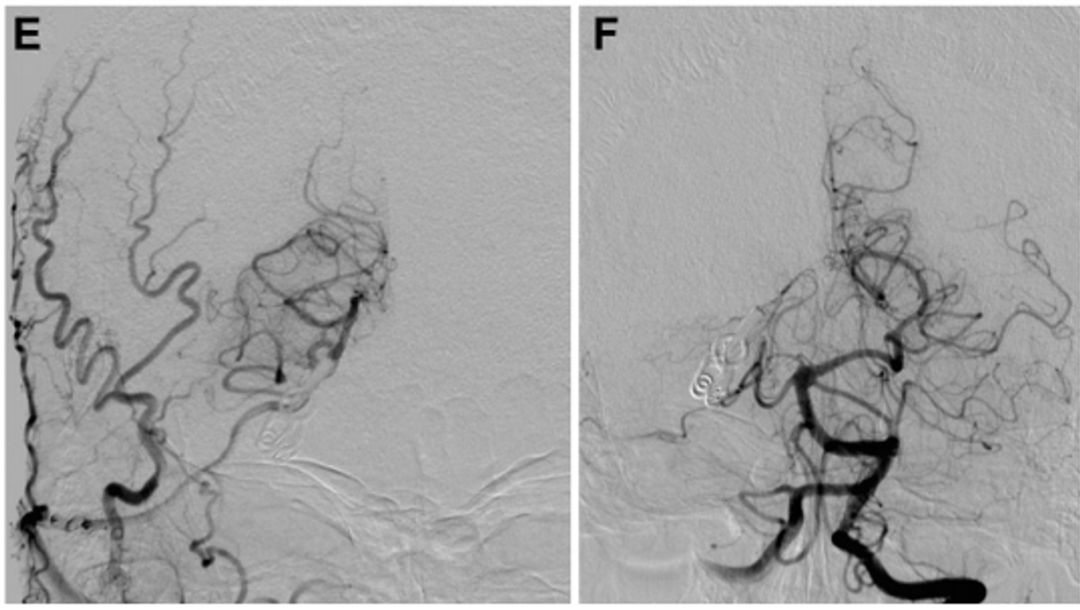

进行STA-PTA旁路手术后,Kawashima教授将远端夹子放置在夹层动脉瘤上,同时保留穿支。术后1周血管造影显示,通过旁路到达左侧PCA区域的血流良好,并且动脉瘤完全被排除(图3E)。两周后,患者出院回家,没有出现神经功能缺损。在1年随访中,患者改良Rankin评分为0,搭桥术仍然合适。

▼E:术后1周的颈外动脉血管造影显示整个左PCA的旁路血液供应良好(箭头)